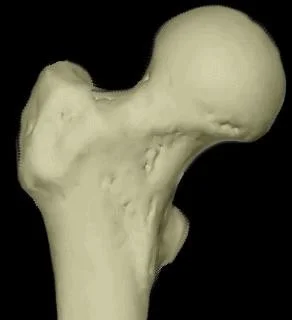

Vascular Supply C ?

- Anterior View

- The Lateral Femoral Circumflex Artery is shown supplying the femoral head.

- Posterior View

- The Medial Femoral Circumflex Artery is depicted as the primary supplier to the femoral head.

Risk of Avascular Necrosis

- Risk of osteonecrosis (Avascular Necrosis)

- More in near head (Sub-capital)

- More in displaced fractures